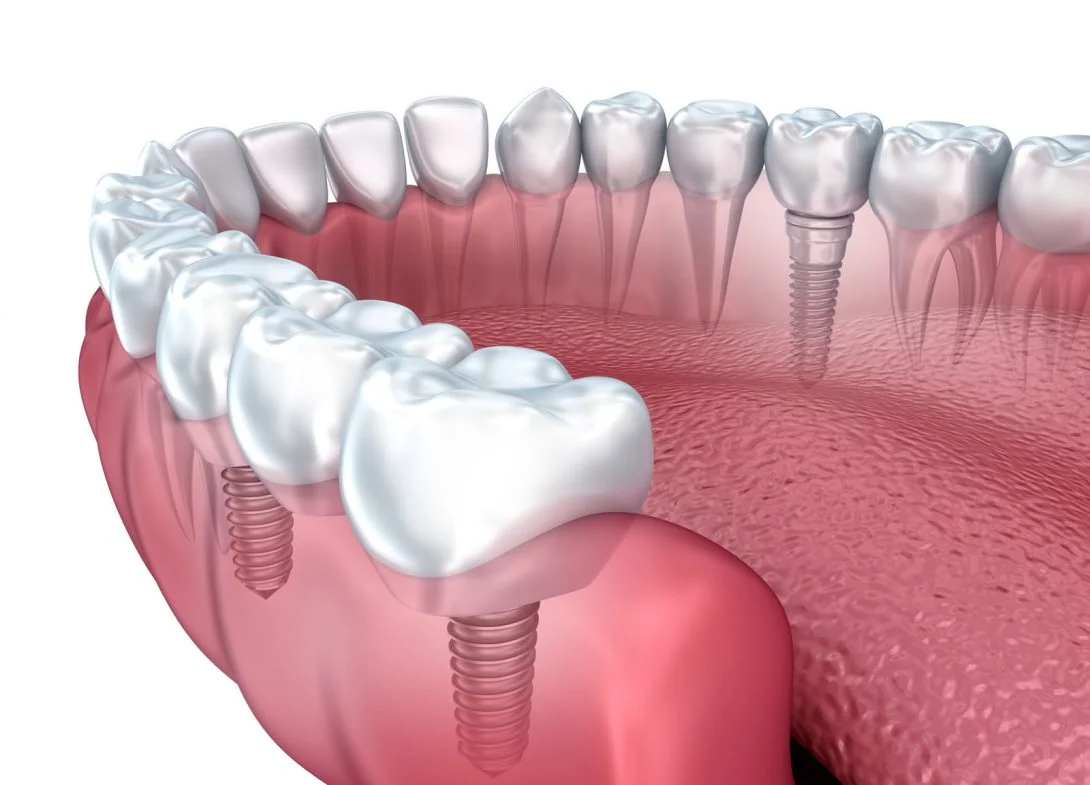

Welcome to Care 32 Dental Clinic & Implant Center, your trusted destination for comprehensive dental care. Located in the heart of the city, we specialize in providing a wide range of dental treatments to ensure the health and beauty of your smile. Our clinic offers advanced technology, a professional team of experts, and a comfortable environment to make your visit stress-free and effective. Whether you're in need of a routine check-up or complex dental procedures, we provide the highest standards of care with personalized attention to meet your needs.